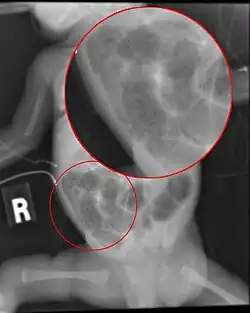

Diagnosis is usually suspected clinically, but often requires the aid of diagnostic imaging, most commonly radiography, which can show the intestines and may show areas with dead tissue or a bowel perforation.[18] Specific radiographic signs of NEC are associated with specific Bell's stages of the disease:[19]

- Specific radiologic signs (pneumatosis intestinalis or portal venous gas)

- Severe radiologic signs (pneumoperitoneum)

Ultrasonography has proven to be useful, as it may detect signs and complications of NEC before they are evident on radiographs, specifically in cases that involve a paucity of bowel gas, a gasless abdomen, or a sentinel loop.[21] Diagnosis is ultimately made in 5–10% of very-low-birth-weight infants (<1,500g).[22]

-

Esophagus, stomach and intestines of affected infant showing intestinal necrosis, pneumatosis intestinalis, and intestinal perforation (arrow) (autopsy specimen) -

Close-up of intestine showing extensive necrosis (autopsy specimen)

Diagnosis of NEC is more challenging in premature infants, due to inexplicit symptoms and radiographic signs. The most preterm infant is at highest risk of developing NEC.[23]